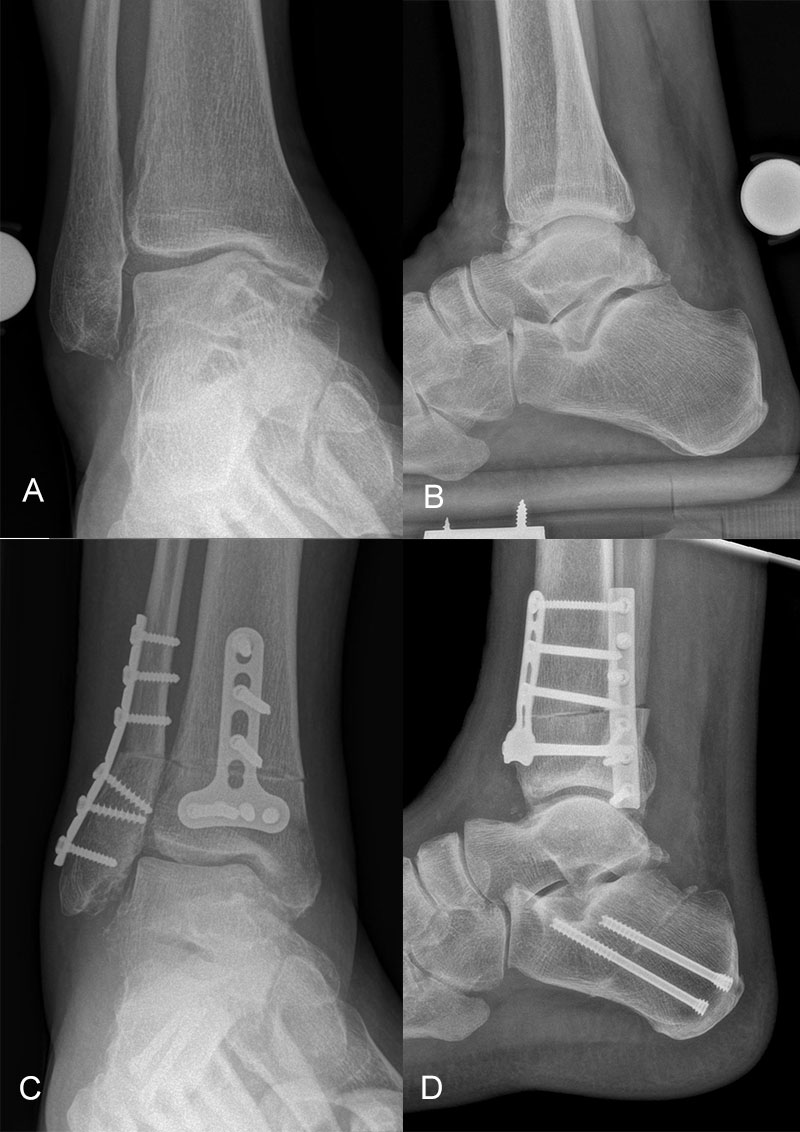

Supramalleoläre Korrektur-Osteotomien

Patienten mit frühen Stadien einer Arthrose am Sprunggelenk sollten auf mögliche bestehende Achsabweichungen hin untersucht werden. Valgus- oder Varus-Deformitäten des Rückfußes und des Unterschenkels zeigen pathologisch veränderte Druckverteilungsmuster insbesondere im OSG, was langfristig zur Entwicklung einer asymmetrischen Sprunggelenks-Arthrose führt 116.

Korrektur-Osteotomien können die normale Biomechanik des OSG wiederherstellen und damit den degenerativen Prozess aufhalten bzw. verlangsamen 117.

Die supramalleoläre Osteotomie ist ein gelenkerhaltendes Verfahren, das der Behandlung des exzentrischen Knorpelverlustes infolge einer übermäßigen Varus- oder Valgusfehlstellung vorbehalten ist. Der Grad der supramalleolären Fehlstellung hat einen signifikanten Einfluss auf die Kraftübertragung auf die Gelenkoberfläche 119. Die daraus resultierende fokale statische und dynamische Überlastung im Gelenk führt zu einer raschen Degeneration der Gelenkoberfläche 116120.

Supramalleolare Osteotomien werden durchgeführt, um die mechanische Achse neu auszurichten und so die Belastung im Sprunggelenk neu zu verteilen, mit dem Ziel, die degenerative Kaskade zu verzögern oder zu stoppen 118121122

Indikationen für eine supramalleoläre Osteotomie sind asymmetrische Valgus- oder Varusarthrosen mit mindestens 50% erhaltener tibiotalarer Gelenkoberfläche. Kontraindikationen sind ältere Patienten mit einer Instabilität des Rückfußes, die durch eine Bandrekonstruktion nicht behoben werden kann, Patienten mit schweren vaskulären oder neurologischen Erkrankungen der betroffenen Extremität, entzündlichen Arthritiden und aktive Infektionen.

Ein Vorteil der medialen öffnenden Osteotomie ist die Möglichkeit der Korrektur von Fehlstellungen in der coronaren und sagittalen Ebene. Nachteilig ist die Notwendigkeit eines zusätzlichen Zugangs, falls der Patient eine Fibulaosteotomie benötigt.

Die lateral schließende Osteotomie hat den Vorteil, leicht auf die Fibula zuzugreifen, die Notwendigkeit einer eventuellen Knochentransplantatinsertion zu umgehen, sowie die inhärente Stabilität des Konstrukts zu erhöhen. Zudem werden die Weichteile weit weniger kompromittiert 123124

Für die Korrektur einer Valgus-Fehlstellung empfehlen die meisten Autoren eine medial schließende Osteotomie mit dem Ziel einer Überkorrektur von 2-4° Varus. Eine zusätzliche Fibulaosteotomie durch einen separaten lateralen Zugang ist erforderlich, wenn die Talusreposition durch die Fibula blockiert ist. Eine medial öffnende Osteotomie kann ebenfalls in Betracht gezogen werden, ist jedoch kontraindiziert bei schlechten medialen Weichteilen. Die mediale Kortikalis ist ebenfalls schwächer als lateral und kann zu einer Überkorrektur führen.

Sobald eine supramalleoläre Korrektur erreicht ist, müssen verbleibende Fehlstellungen, Kontrakturen und Instabilitäten ebenfalls behoben werden. Dies betrifft vor allem eine mögliche Kontraktur des Subtalargelenks, der Tibialis posterior-Sehne, eine Fehlstellung des Rückfußes, oder eine Kollateralband- und Peroneus brevis-Insuffizienz. Ein Korrekturverlust kann auftreten, wenn diese Pathologien nicht bzw. nicht ausreichend adressiert wurden 121125.